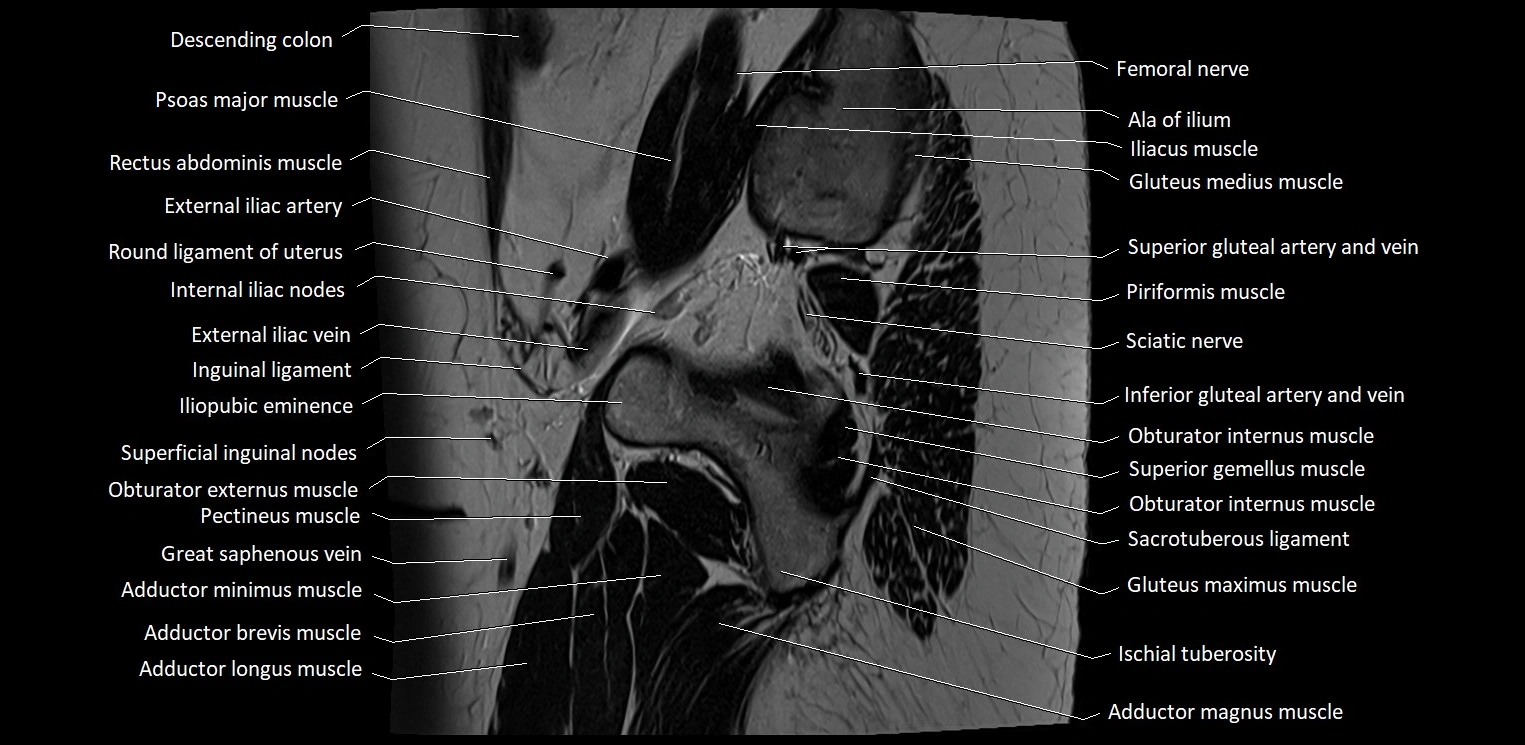

- Adductor brevis muscle

- Adductor longus muscle

- Adductor magnus muscle

- Adductor minimus muscle

- Ala of ilium (wing of ilium)

- Deep femoral artery (profunda femoris)

- External iliac artery

- External iliac vein

- Femoral nerve

- Gluteus maximus muscle

- Gluteus medius muscle

- Iliopubic eminence

- Inferior gemellus muscle

- Inferior gluteal artery

- Inferior pubic ligament

- Inguinal ligament

- Obturator externus muscle

- Obturator internus muscle

- Pectineus muscle

- Piriformis muscle

- Psoas major muscle

- Round ligament of uterus

- Sacrotuberous ligament

- Sartorius muscle

- Sciatic nerve

- Superficial inguinal lymph nodes

- Superior gemellus muscle